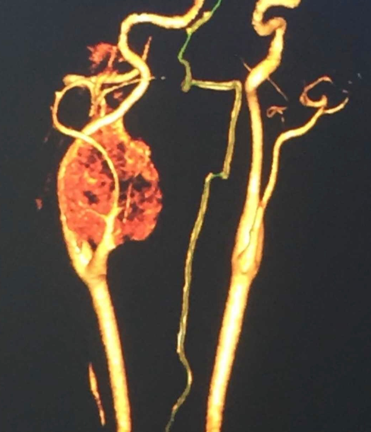

The figure 2 shows the MRA that helped us explain the vascular nature of the tumor and extent of the growing structure. These images helped in the final diagnosis of carotid body paraganglioma that was relatable with high blood pressure and the probable site of the presence of glomus cells, the primary site of this tumor.